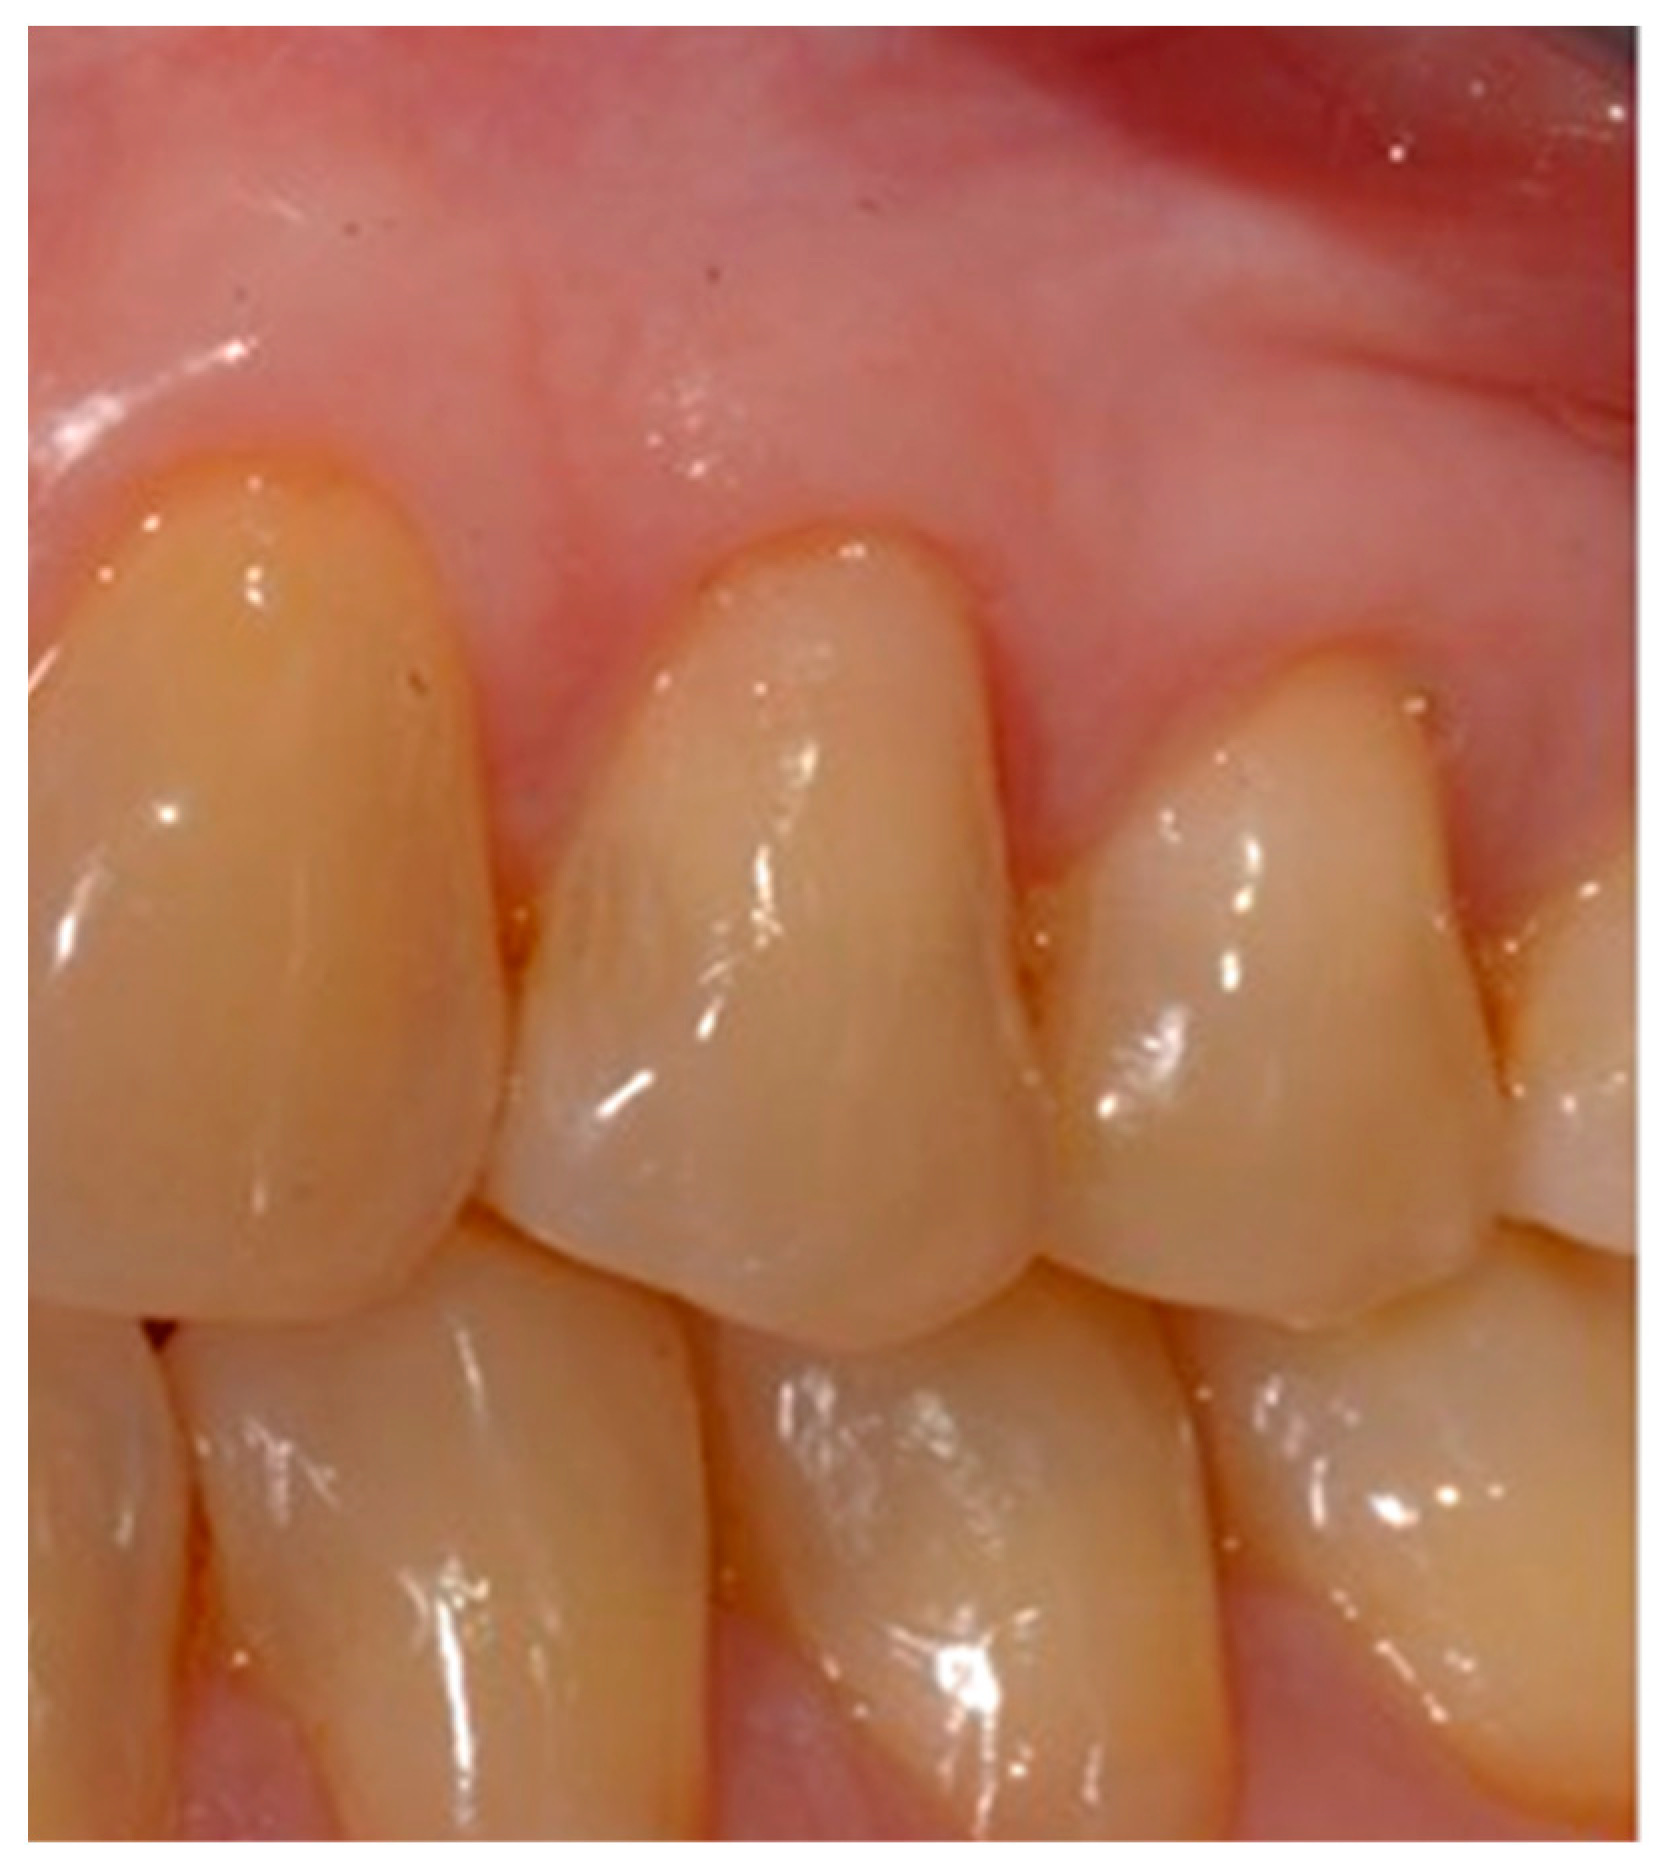

- Finishing the restoration with a coarse- (80 μm) and a fine- (50 μm) grain flame bur placed on the most apical point of the restoration, without touching the dental tissue with the tip, in order to create an angle of approximately 45° and maintain a convex profile (Figure 8).

- Polishing the restoration with fine-grained 50 μm diamond burs, composite polishers and a brush with bristles impregnated with silicon carbide to give the restoration a perfect shine.